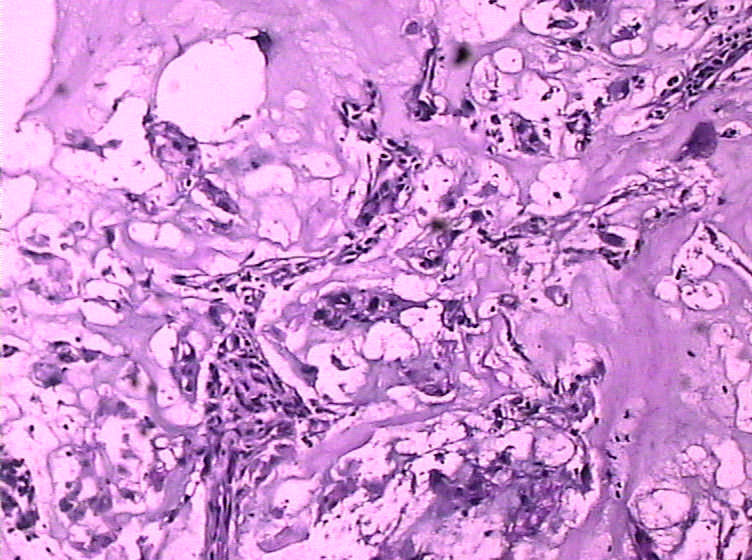

女,4岁,咽喉壁肿物。